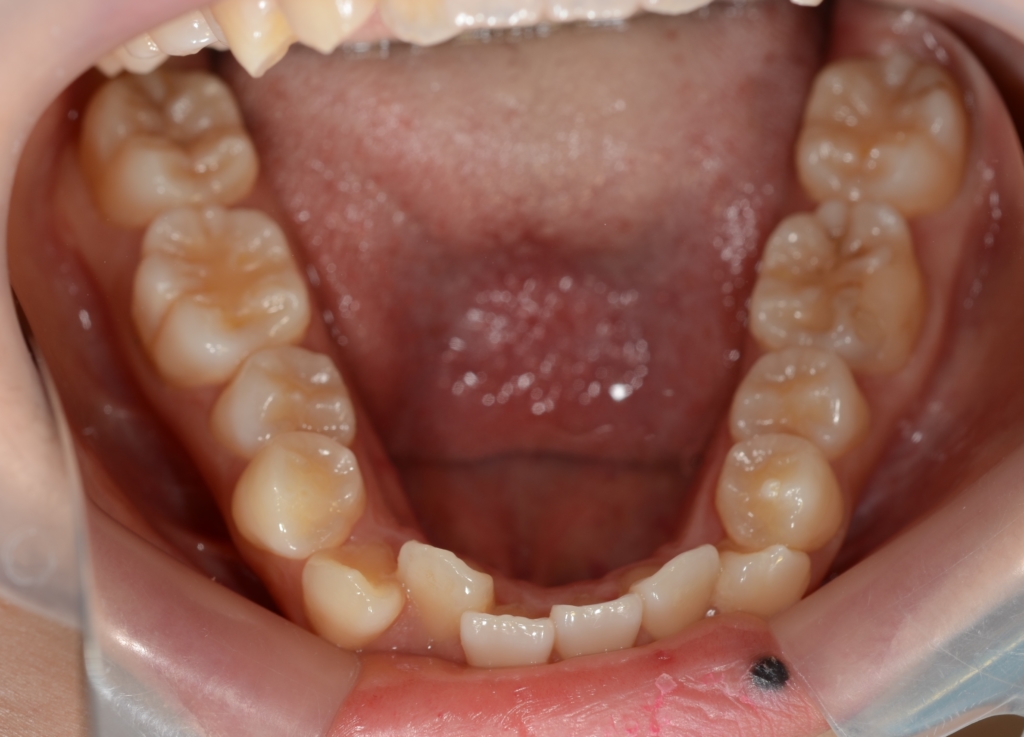

【Before】

レントゲン写真で確認すると、

この患者さんの場合、

#1.顎と歯の不調和による叢生

(前歯部の反対咬合を伴う)

#2.骨格的に下顎前突(受け口)傾向